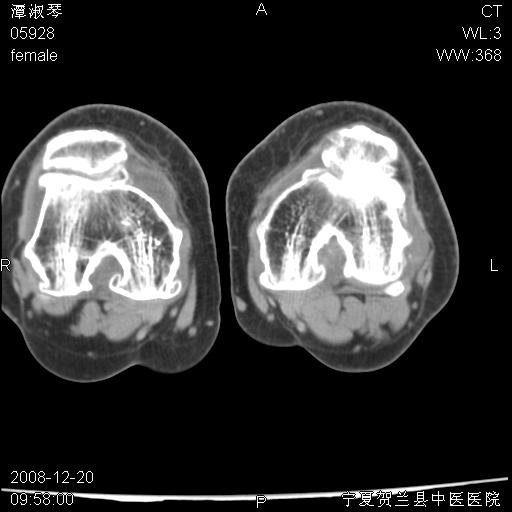

标题: CT17526:请各位看看是啥? [打印本页]

标题: CT17526:请各位看看是啥?

内生软骨瘤?骨梗死?

考虑内生软骨瘤可能性大

考虑-----骨梗死+退变

支持骨梗死,退行性骨关节病,膝关节积液.

考虑骨梗死可能性大

支持骨纤或内生软骨瘤或骨梗死,退行性骨关节病,膝关节积液.

骨梗死可能性大

左股骨下段骨梗死。双膝退变。

支持:内生软骨瘤或骨梗死!另:退行性骨关节病,膝关节积液。

左胫骨下端松质骨及髓腔内可见点片状高密度灶,骨皮质无明显膨胀及变薄。病变范围较长。支持骨梗死,退行性骨关节病,膝关节积液